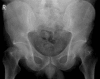

Ankylosing spondylitis (AS) is a complex, potentially debilitating disease that is insidious in onset, progressing to radiological sacroiliitis over several years. Patients with symptomatic AS lose productivity owing to work disability and unemployment, have a substantial use of healthcare resources, and reduced quality of life. The pathogenesis of AS is poorly understood. However, immune mediated mechanisms involving human leucocyte antigen (HLA)-B27, inflammatory cellular infiltrates, cytokines (for example, tumour necrosis factor alpha and interleukin 10), and genetic and environmental factors are thought to have key roles. The detection of sacroiliitis by radiography, magnetic resonance imaging, or computed tomography in the presence of clinical manifestations is diagnostic for AS, although the presence of inflammatory back pain plus at least two other typical features of spondyloarthropathy (for example, enthesitis and uveitis) is highly predictive of early AS. Non-steroidal anti-inflammatory drugs (NSAIDs) effectively relieve inflammatory symptoms and are presently first line drug treatment. However, NSAID treatment has only a symptomatic effect and probably does not alter the disease course. For symptoms refractory to NSAIDs, second line treatments, including corticosteroids and various disease modifying antirheumatic drugs, are employed but are of limited benefit. Emerging biological therapies target the inflammatory processes underlying AS, and thus, may favourably alter the disease process, in addition to providing symptom relief.